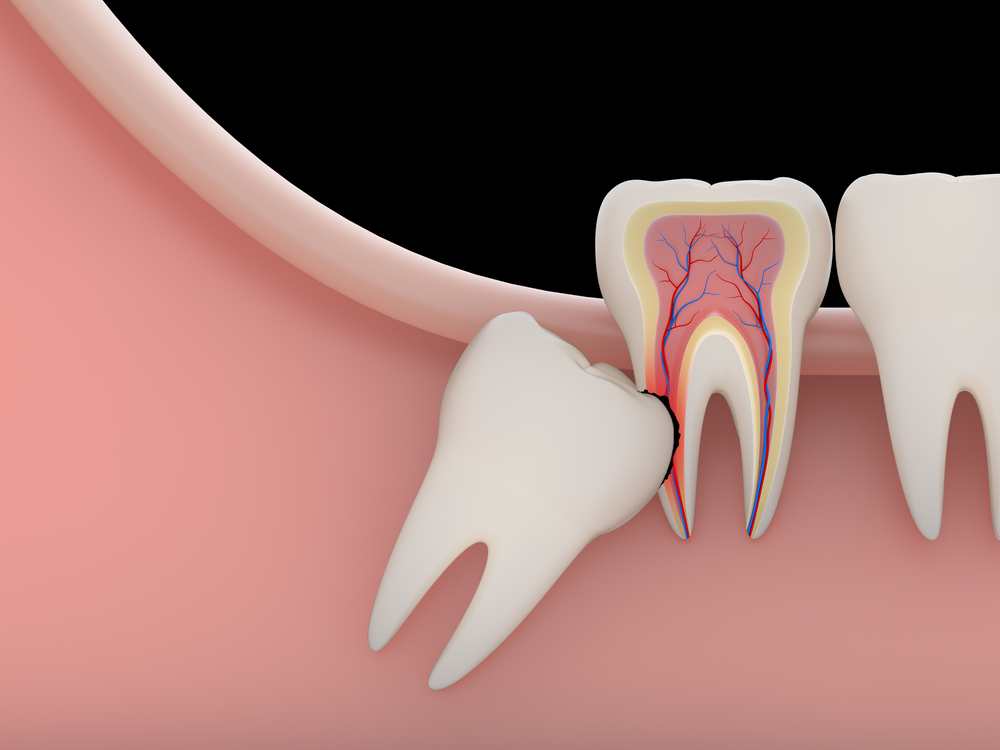

Cirugía oral (extracciones y muelas del juicio)

Cuando un diente no se puede conservar o una muela del juicio da problemas, realizamos la extracción con técnicas cuidadas y una experiencia cómoda, explicando siempre el postoperatorio y los pasos a seguir.

¿Cuándo es necesaria una extracción dental?

Se indica cuando un diente no se puede conservar de forma predecible (fractura, caries muy avanzada, infección, muelas del juicio con problemas, etc.). Siempre valoramos primero opciones conservadoras y te explicamos el porqué.